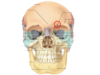

Reconozca la marca ósea encerrada en el círculo

Agujero – foramen supraorbital